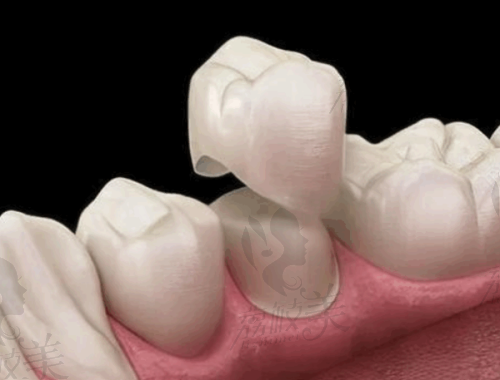

王医生较大的标签,两个字:安心。他主张“看得懂的种牙”,所有治疗步骤都会提前3D可视化模拟,让患者“一眼明白要干啥”;手术过程主打微创、少缝合、大程度保留骨组织,几乎达到了“今天种牙、明天吃肉”的速度。同时,他打破传统“种牙冷冰冰”的印象,把诊室变成“减压脱口秀”,据说有不少患者笑着就种完了一口牙。

一句话概括:“种得准+种得快+种得稳”。无论是50岁的“怕疼大叔”,还是30多岁的“追求美学小姐姐”,在王医生这里都能得到个性化方案。他常说:“种牙其实就像盖房子,基础稳、结构合理、外观精致,牙齿也一样能‘一直住得舒服’。”不少种完牙的患者反馈吃饭比以前更香,人也变得爱笑了——如果这不是种植的魅力,那什么才是呢?